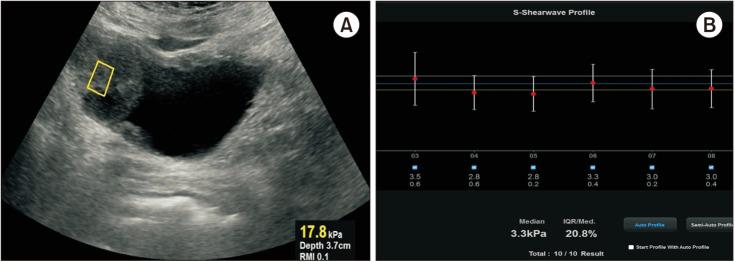

Patients with microscopic or macroscopic hematuria diagnosed with bladder tumors were included. SWE measurements were performed using a Samsung Medison RS80A Prestige ultrasonography device, with ten valid measurements taken for each tumor. Tumor specimens were collected via transurethral resection (transurethral resection of the bladder tumor) for histopathological analysis. Microvessel density (MVD) was assessed by immunohistochemical staining with anti-CD34 antibody using the hot-spot method. Correlations between tissue stiffness, MVD and tumor stage and grade were analyzed, and receiver operating characteristic (ROC) analysis determined the optimal SWE cutoff for differentiating tumor characteristics.

A total of 65 bladder urothelial carcinoma patients were included in the study (43 high-grade, 22 low-grade). SWE and MVD were significantly higher in the high-grade group (p=0.001, p=0.002, respectively). ROC analysis showed SWE could differentiate tumor grades (area under ROC curve=0.837, p<0.001), with a cut-off of 4.25 kPa (74% sensitivity, 86% specificity). Stiffness was also higher in recurrence (p=0.007). A strong positive correlation between SWE and MVD was found (rho=0.767, p<0.001). SWE may be a reliable, non-invasive tool for assessing tumor grade and recurrence risk.

本研究共纳入65例膀胱尿路上皮癌患者(43例高级别,22例低级别)。高级别组的SWE和MVD显著更高(分别为p = 0.001,p = 0.002)。ROC分析显示SWE可区分肿瘤分级(ROC曲线下面积 = 0.837,p < 0.001),临界值为4.25 kPa(敏感性74%,特异性86%)。复发患者的硬度也更高(p = 0.007)。发现SWE与MVD之间存在强正相关(rho = 0.767,p < 0.001)。SWE可能是评估肿瘤分级和复发风险的可靠、非侵入性工具。